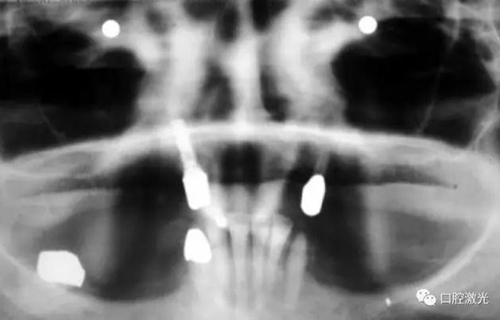

患者女性,43歲。在18年前在13位置上安裝種植體。整個上顎除23外,牙盡缺失。安裝種植體后,在種植體及23上固定套筒冠義齒。3年后患者發現刷牙時,臨近13有大量出血現象。通過探針檢查發現深度達6mm。

對患者實施局部麻醉,隨后在種植體位置進行翻瓣。利用塑料刮治器將肉芽組織清除干凈,并將翻瓣邊緣削薄。此時在種植體周圍可見明顯骨缺失。

激光滅菌治療完成后,通過骨移植手術完成骨缺失的填充并縫合。一周后可以拆線。在此之后,第6周和第3個月需要進行復診。最終的對手術區域的檢查確認在6個月時進行。

如今,種植體周圍炎的治療完成已經過去了10多年,上顎義齒的狀況沒有再出現問題。種植體周圍組織基本健康。

治療十年以上恢復情況